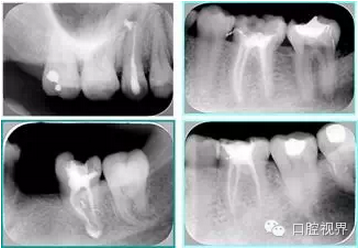

左圖和上圖為干髓治療后牙齒,齲齒疏通后進(jìn)行根管充填。

如圖為塑化加根充處理后牙齒 X 線片。

常見(jiàn)有修復(fù)性鈣化和增齡性鈣化。下面為根管鈣化 X 線片。